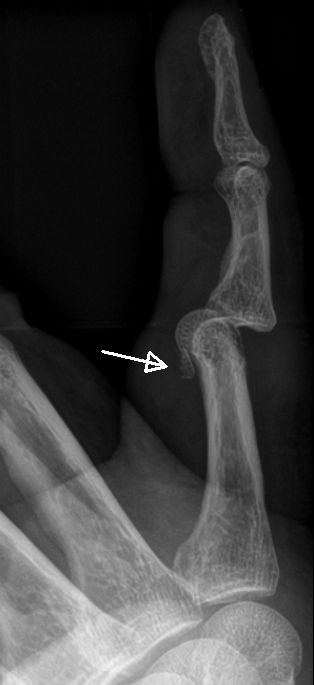

PIP-ledsluxation med volart fragment, reluxerade efter reposition, opererades sedan av handkirurg